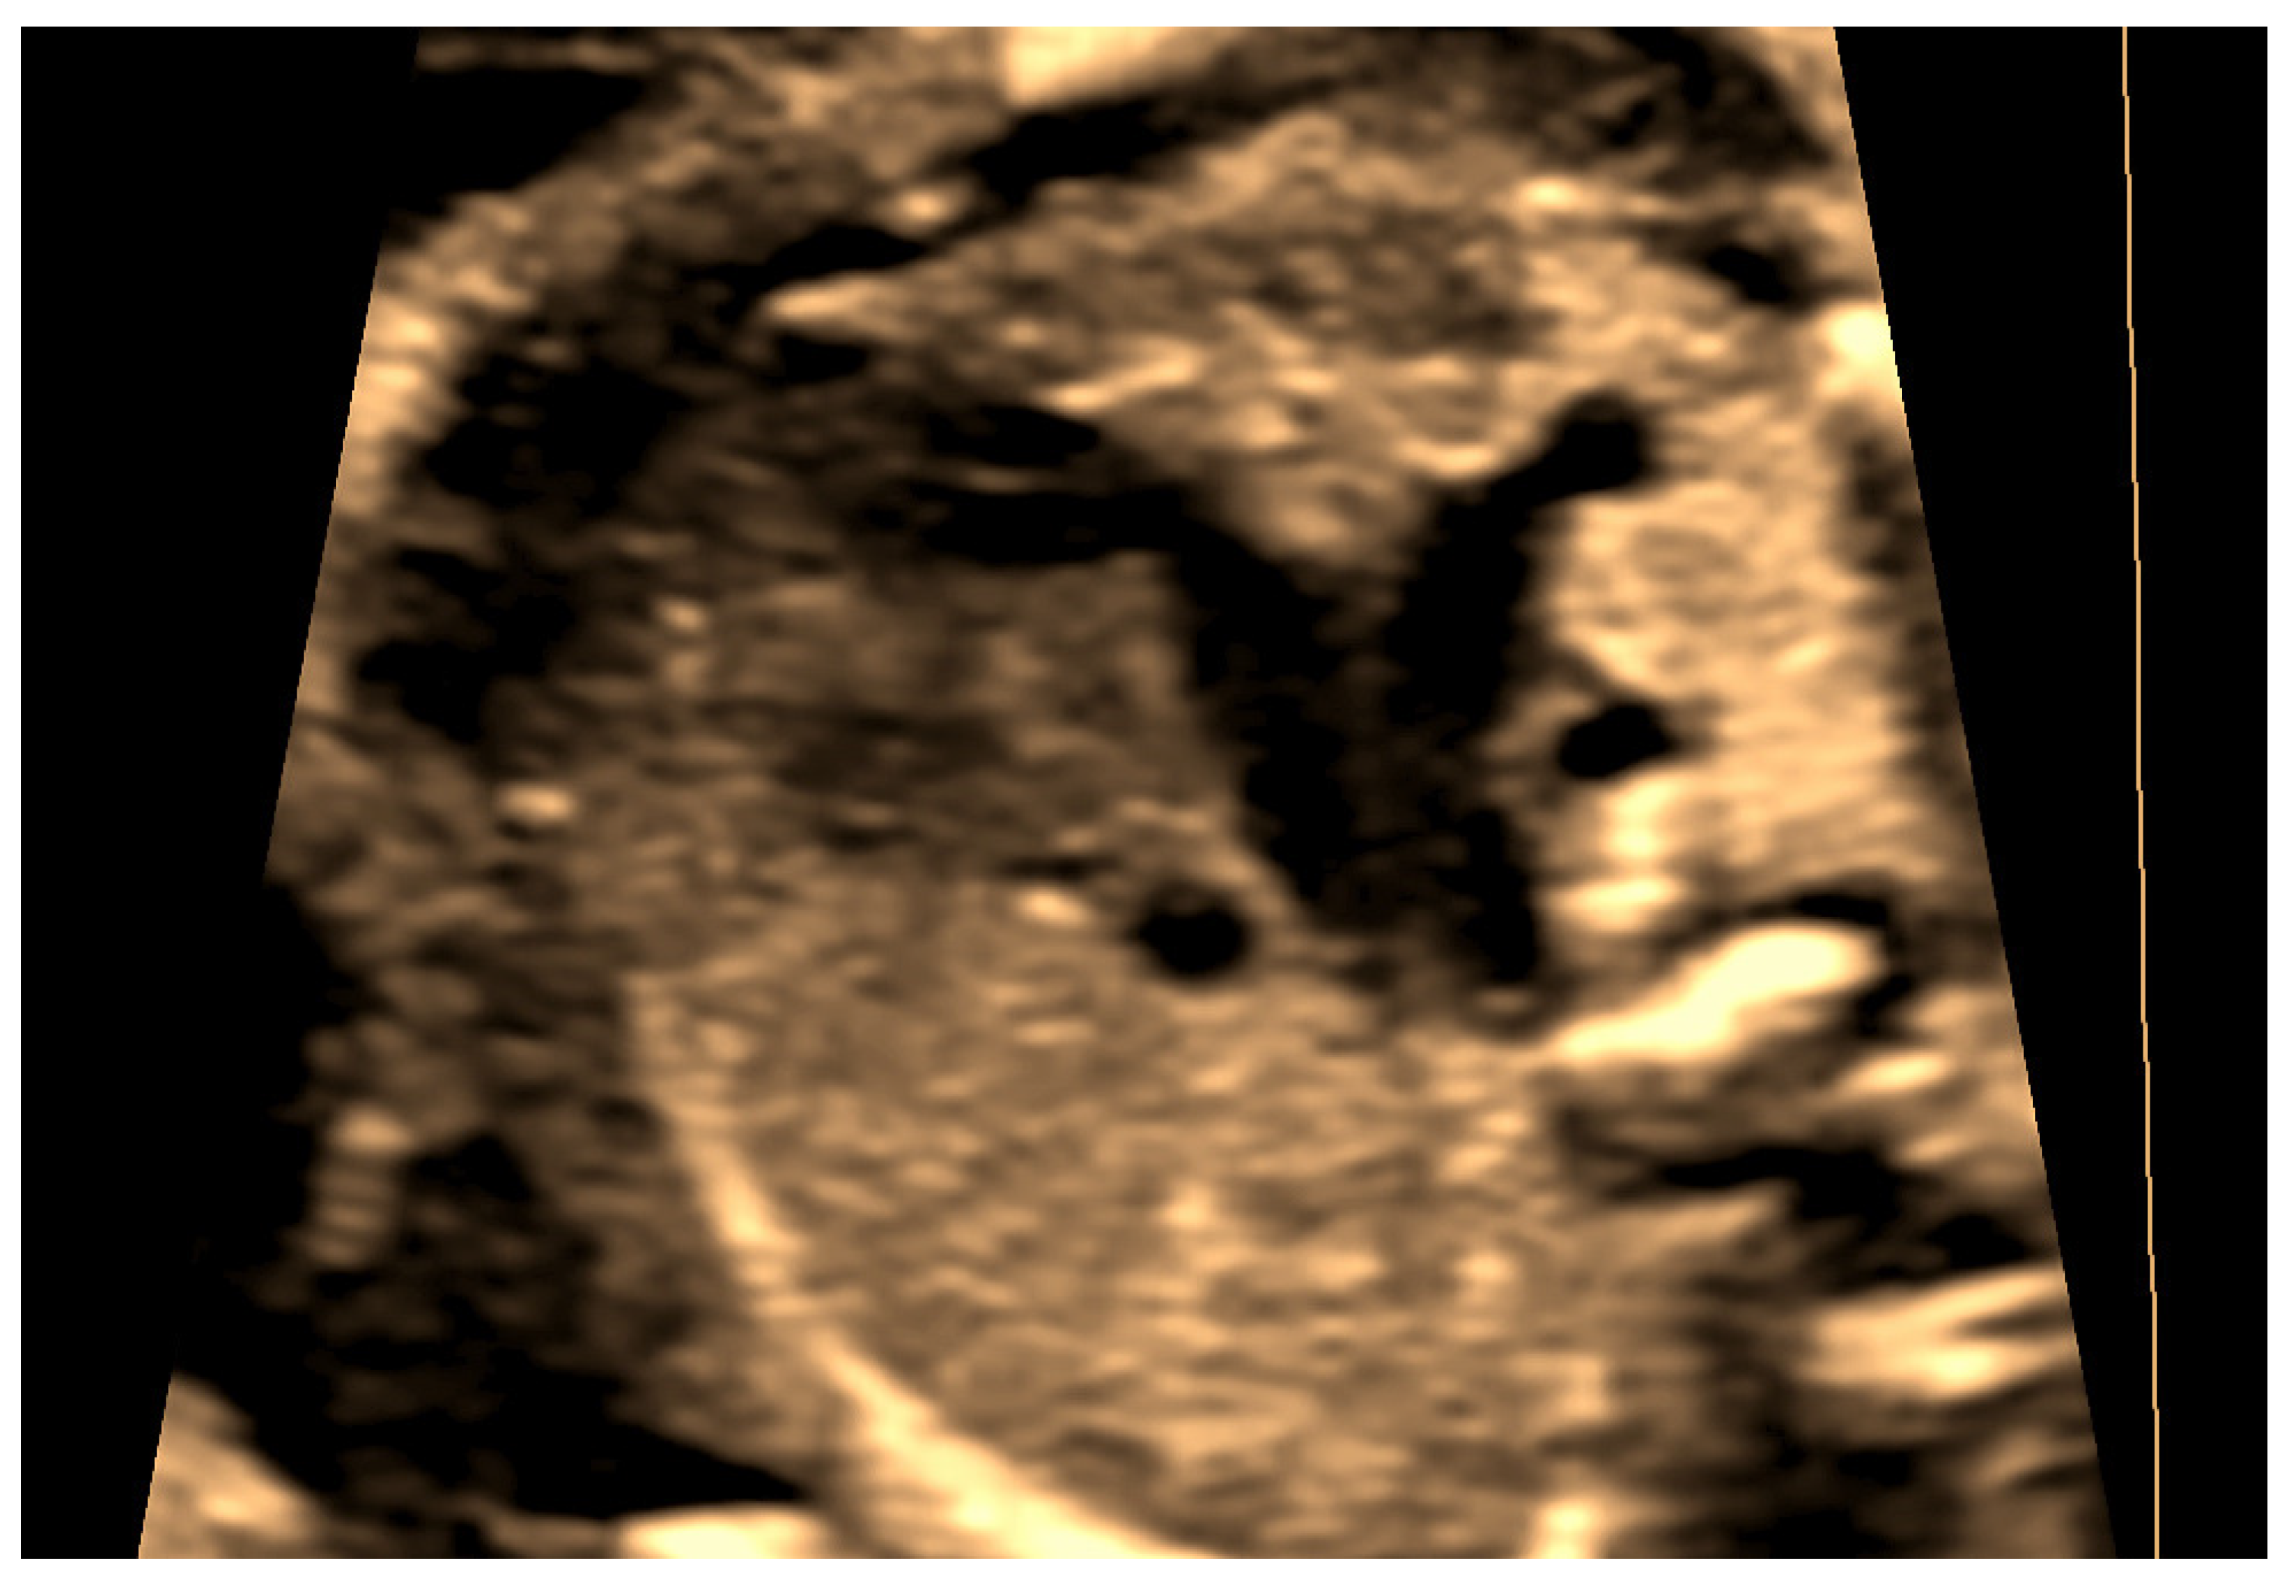

4.1. Case 1